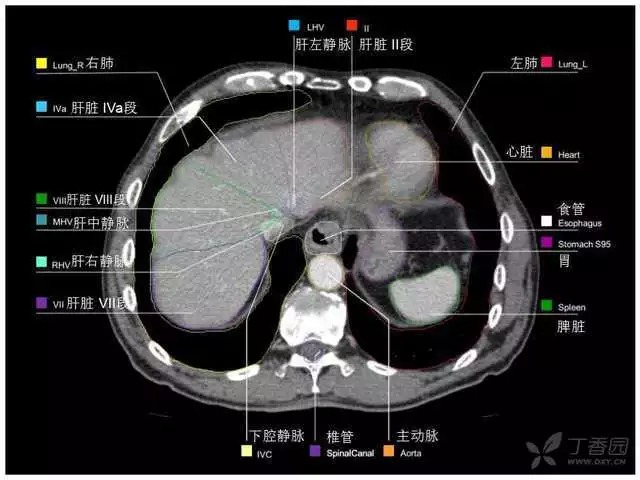

腹部肝脏高清CT断层的图谱

全腹部高清CT图谱,淋巴结彩色图谱,血管解剖图谱大汇总!